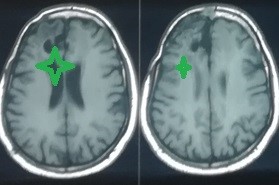

ورم سحائي بالفص الامامي الايمن بالمخ

meningioma in the right frontal lobe of the brain

A transverse view of an MRI scan of a 63-year-old patient suffering from epileptic seizures and weakness on the left side of the body showing a cystic meningioma in the right frontal lobe of the brain shaded in red. And the rays after excision with a microscopic surgery, where he completely disappeared, shaded in green. The pictures during surgery also show the solid part that was completely removed and the location of the tumor in the brain, as the brain after removing the hard part and emptying the cyst around it is completely intact. The patient has fully recovered after the surgery and is living his life normally.